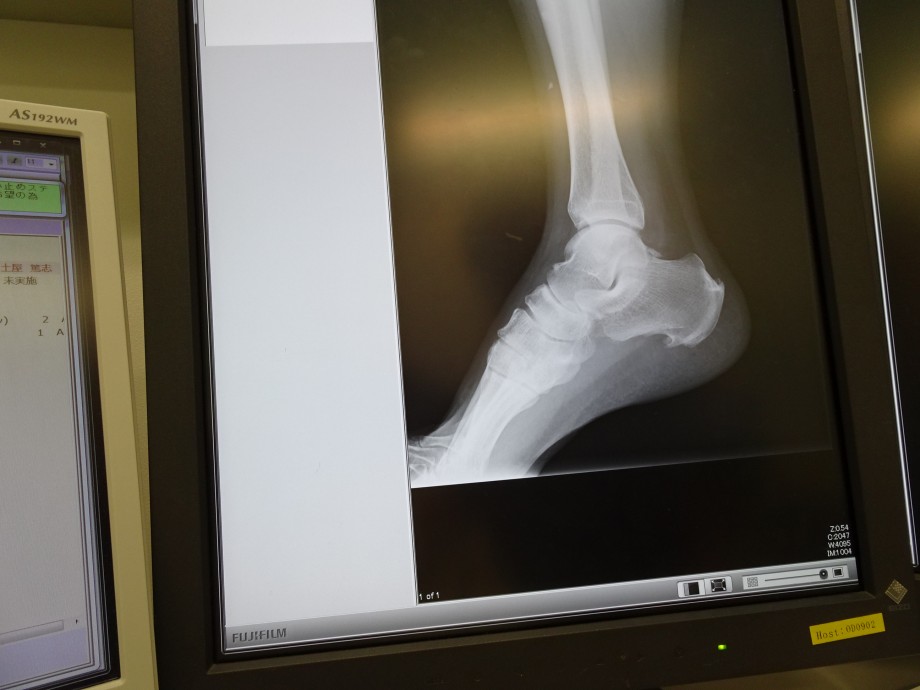

ちなみに、しばらく歩くと痛む足のカカトは絶賛変形中!(笑)